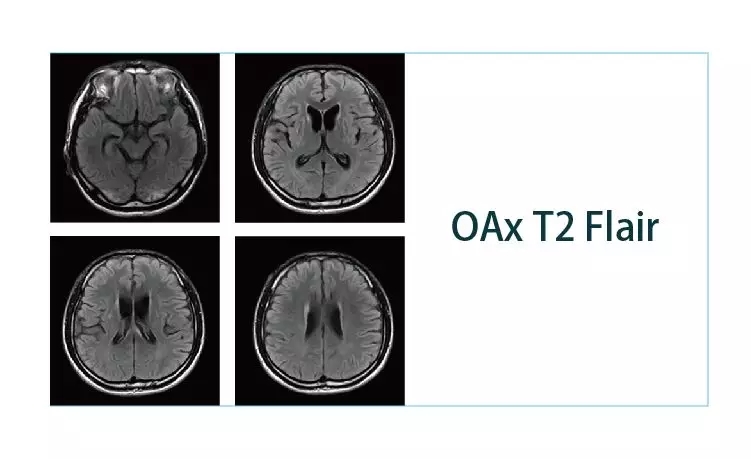

【朗润影像档案】20190111磁共振影像病例结果讨论